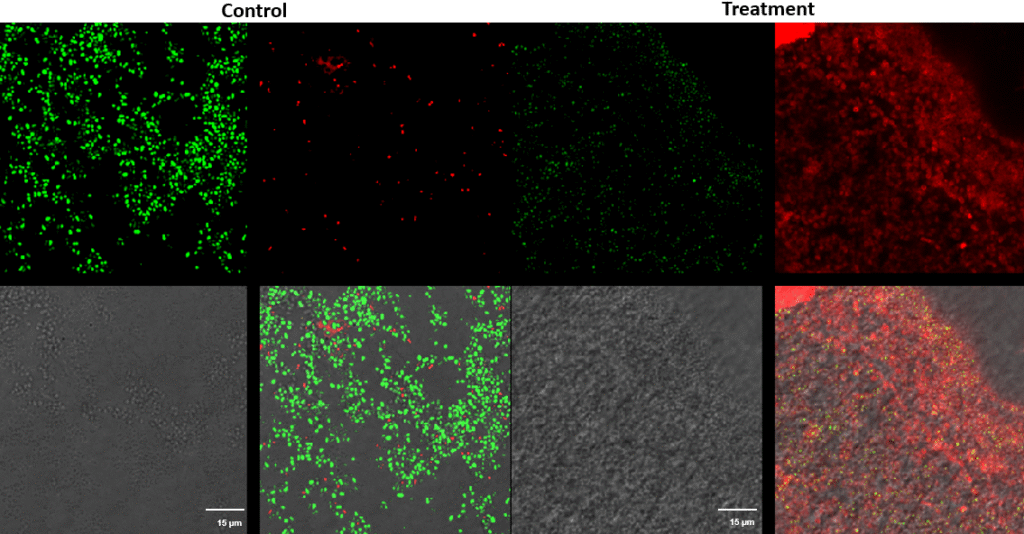

Streptococcus canis – Superficial fluorescence microscopy. Each image is divided into four quadrants: the upper left quadrant shows the green channel highlighting live bacteria; the upper right shows the red channel highlighting dead bacteria; the bottom right shows the merged green and red channels indicating live and dead bacteria; and the bottom left illustrates the bright field image. Bright green represents bacteria with intact membranes (live), red represents bacteria with compromised or dead membranes, and yellow represents bacteria with partially compromised membranes. Scale bar: 15 µm.

Pseudomonas aeruginosa – Superficial fluorescence microscopy. Microscopic imaging of Pseudomonas aeruginosa inoculated on the corneal surface and treated with UV-C for 15 seconds at a 10 mm distance. The images show clear bacterial membrane disruption and reduced viability, demonstrating the antimicrobial effectiveness of UV-C treatment on the superficial corneal layer.

Each image is divided into four quadrants: the upper left quadrant shows the green channel highlighting live bacteria; the upper right shows the red channel highlighting dead bacteria; the bottom right shows the merged green and red channels indicating live and dead bacteria; and the bottom left illustrates the bright field image. Bright green represents bacteria with intact membranes (live bacteria), red represents bacteria with compromised or dead membranes, and yellow represents bacteria with partially compromised membranes. Scale bar: 15 µm.